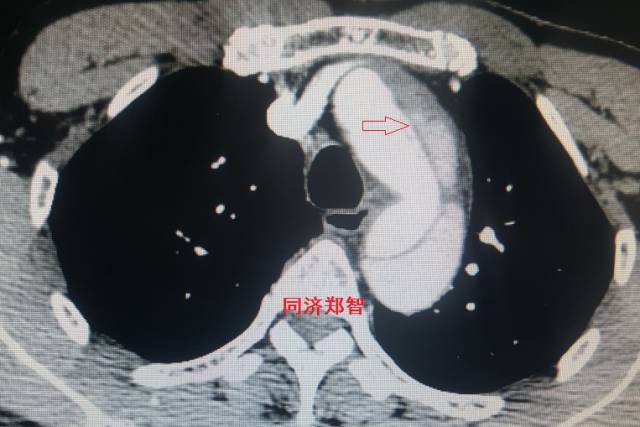

病例十一

平扫CT发现主动脉血管内孤立的钙化点(红色箭头所示),CTA证实为降主动脉溃疡合并壁间血肿。